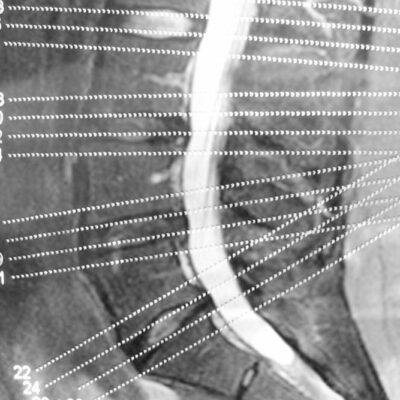

A brief overview of degenerative disc and joint disease

When you mention the term degenerative disease, it refers to the gradual deterioration of the body tissues or cells over the years due to the natural aging process. As we age, our spine starts giving in to the stress of providing flexibility and support to our back. The components of the spine start deteriorating slowly, and you will experience back pain and stiffness in the spine.